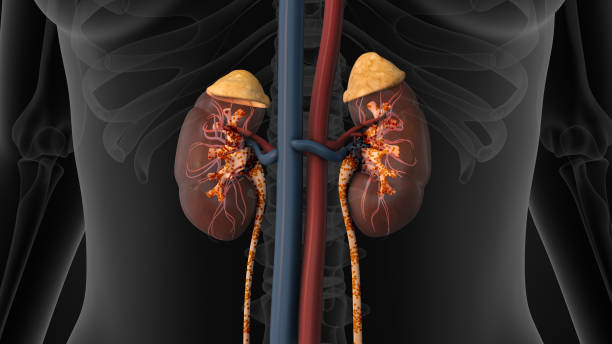

신우신염이란? 상부 요로계에 생긴 세균 감염

신우신염은 **신장과 신우(renal pelvis)**에

세균이 침투해 염증이 발생하는 감염 질환입니다.

대부분 하부 요로계, 즉 방광이나 요도에서 시작된 세균이

상행성으로 올라가 신장 부위까지 확산되며 생깁니다.